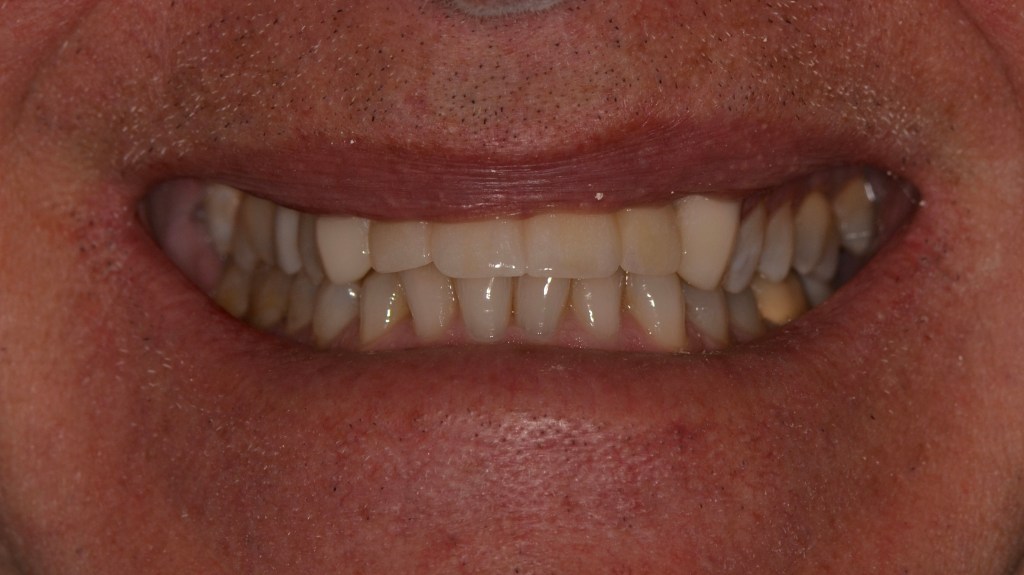

Implant Bridge and Ceramic Crowns